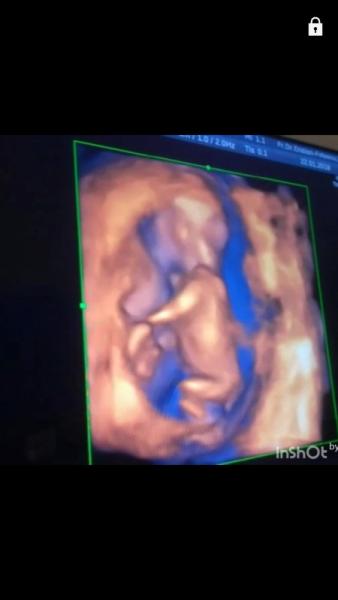

Huhu, was sind eure Tips? Das Bild ist aus der 14ten Ssw..Die Ärztin tippt auf ein Mädel laut Nub Theorie..Was denkt denn ihr so? Mir persönlich ist es egal..Bin halt nur neugierig und habe grade langweile

Das ist der Nub! KEIN Penis..Zu der Zeit haben alle noch den Nub und je nachdem im welchen Winkel er sich befindet kann man sagen was es wird...dachte vielleicht haben eure Ärzte davon auch ein Bild gemacht und sich dazu geäußert..Aber das können nur mindestens Degum 2 Ärzte..lg

Hab versucht den Winkel zu messen..Bin aber glaube ich zu doof